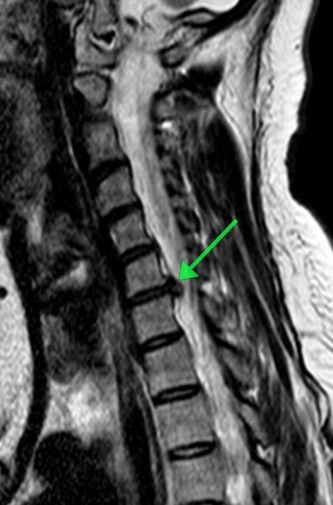

Пациентка обратилась с жлобами на изматывающую боль в руке. Ей провели МРТ, которое показало, что в шейном отделе сформировалась грыжа размером 8 мм. По словам медиков, образование сдавливало спинномозговой канал и корешковое отверстие, угрожая двигательной функции.